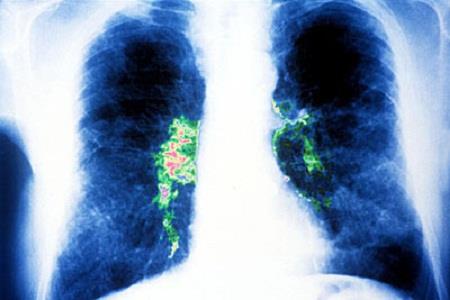

Vi khuẩn này khi xâm nhập vào cơ thể sẽ gây bệnh nhiễm trùng phổi (viêm phổi) - Legionnaires.

Legionella pneumophila khi xâm nhập vào cơ thể sẽ gây bệnh nhiễm trùng phổi.

Legionella pneumophila xâm nhập vào phổi qua đường hô hấp.